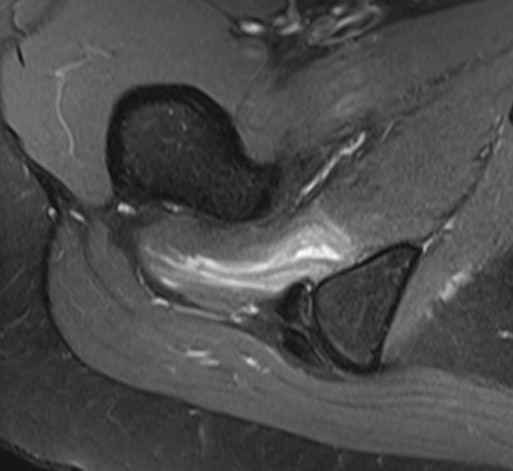

MRI

Reduced ischiofemoral space - distance between the lesser trochanter and the ischial tuberosity

Reduced quadratus femoris space - distance between hamstring tendon and iliopsoas

Inflammation / edema in quadratus femoris +/- fatty degeneration

IFIIFI

IFIIFIIFI